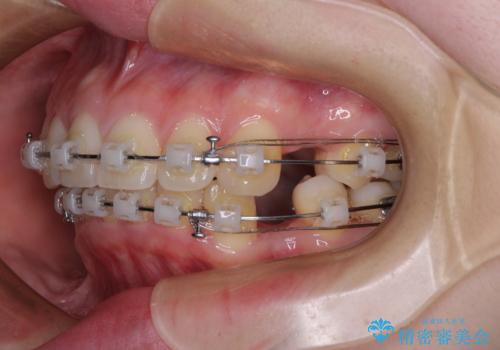

- 矯正装置

- クリアブラケット

- 下唇に跡がつくほどに飛び出した上顎前歯を気にして来院された患者様です。

来院された時から4本の抜歯が必要であることを理解されていらしており、通法通り上下左右の第一小臼歯4本を抜歯し、ワイヤー装置にて矯正治療を行うこととしました。

順調に治療が進み、2年弱で想定していたとおりの仕上がりにて治療を終えることができました。